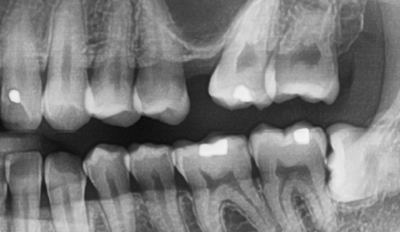

![[서울시청역치과] 20대, 30대도 임플란트를 하나요?? +네비게이션임플란트안내 관련 이미지 1](https://pub-9f2bb3498faf4d1d8714b41df24753e3.r2.dev/content/clinics/archive/rseeanjxfu/naver_blog/yonseiyegam/assets/by_hash/d18cd07061d4bba571af713d6554fcb4769b21eb6c2aa7e0e23d58255342b9f9.jpg)

위 사진은 이가 너무 많이 썩어 뿌리만 남고 이 머리가 부러진 환자분의 치아 사진입니다.

이렇게 치아 머리부분이 거의 없다면 머리 부분을 회복시킬 수 없기 때문에

또는 어떻게어떻게 해서 머리부분을 만들어도 얼마 못쓰고 금방 부러질 것이 뻔하기에

남은 부분을 발치하고 임플란트를 하게 됩니다.